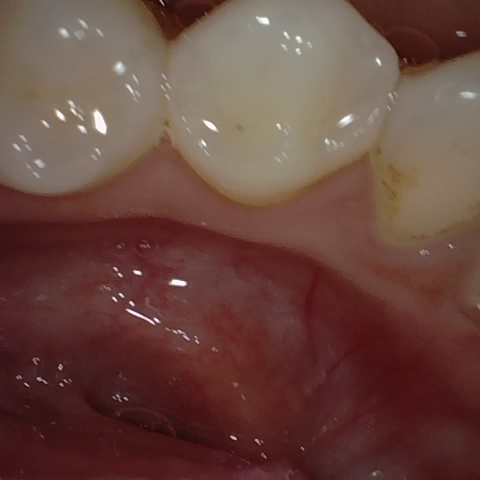

Annotated as "Bad"